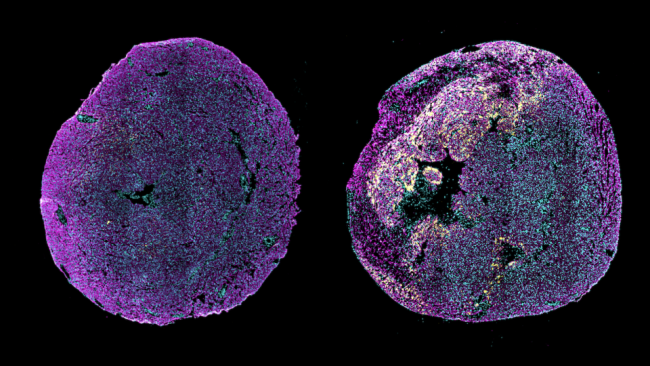

The researchers next tested a single injection of saRNA-LNPs immediately after a heart attack in a mouse model. Treated mice had significantly improved heart function 28 days later compared to untreated mice. They also had less dead heart tissue and reduced scarring. Giving the treatment a week after the heart attack had similar beneficial effects but wasn’t as effective as immediate treatment.

The treatment provided similar benefits after heart attack in other animal models. These included aged mice, mice with atherosclerosis, mouse models of type 2 diabetes, and pig models.

The use of saRNA was key to the treatment’s effectiveness. Treatment with conventional RNA encoding pro-ANP that could not copy itself did not reduce the damaging effects of a heart attack. Importantly, the treatment did not cause any signs of systemic toxicity or abnormal changes to major organs. The only immune reaction to the treatment was some passing local inflammation.